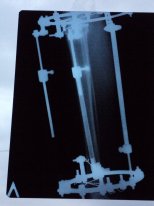

Добрый вечер! Отправляю снимки. Жду ответа.

Вложения

5.JPG

3.JPG

1.JPG

Галина, вечер добрый! Качество снимков ужасное, детально судить о возможности снятия аппаратов, не представляется возможным. Для перестраховки приезжайте в клинику через 2 недельки. Если делать рентген, то надо снимать голень с захватом коленного сустава в 2-х проекциях.